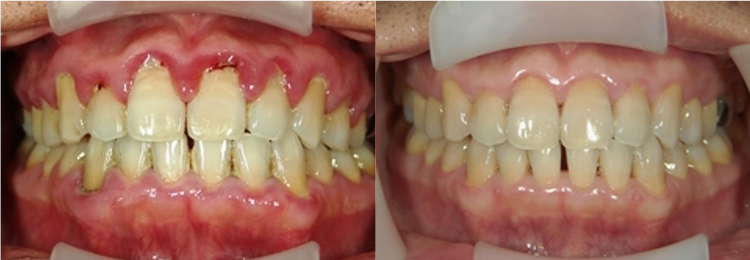

当院では歯周病治療の症例を患者様同意の元で公開しておりますが、歯周病でお困りの患者様に対して当院が経験してきた全てを注ぎ込んで治療にあたっています。

当院が選ばれる理由の一つが症例が豊富であることです。治療結果を掲載できることは、患者様と二人三脚で治療してきた結果であり、治療に対するこだわりと信念を表していると考えています。